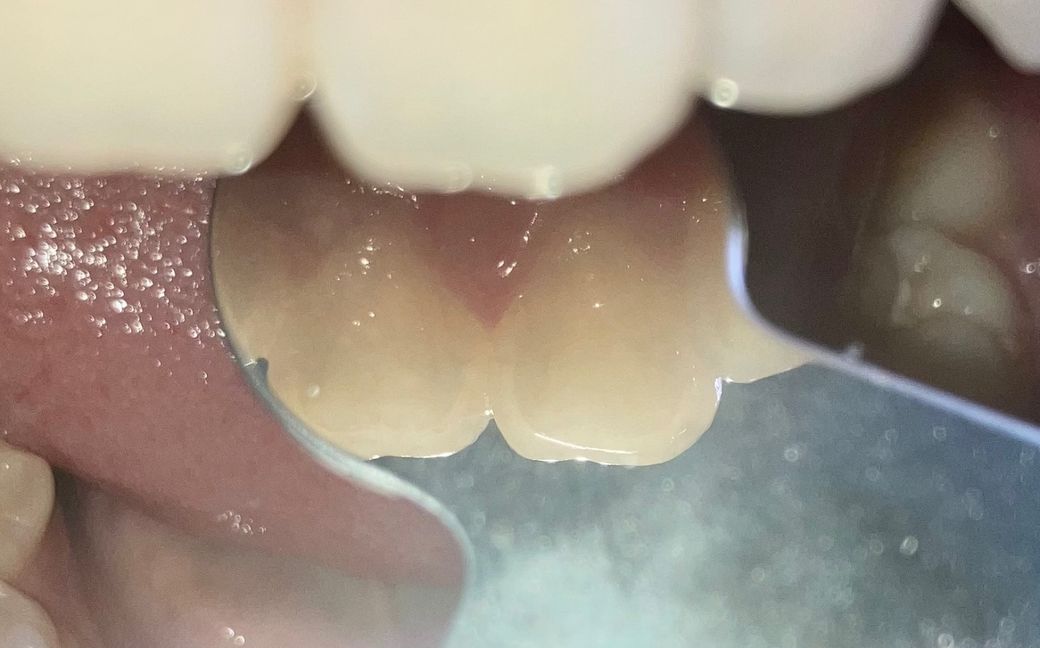

앞니 사이 충치 레진한 부분 치실했는데 조각 같은게 나왔어요(사진 첨부)

앞니 사이 충치로 레진을 했는데 사이를 꽉 막아놔서 치실 할 필요가 없다고 하셨어요.. 치실이 안 들어간다고 하니까 몇달 후면 들어가니까 그때 하고 안 들어가면 계속 안 해도 된다고 하셨거여

완전 다 넣지도 않았고 적당히 넣었다 빼려는데 반투명?하고 얇고 판판한 조각같은게 딸려나왔어요

음식물은 아니에요.. 도자기조각같은..얇은 조각이었어요

레진은 뒷면에서 했는데 앞에서 보면 뭔가 있어서 신경쓰였거든요

두 장은 어제 찍은 사진이에요..

• 1번 째 사진

레진이 떨어진 것으로 보이진 않고 레진 접착제가 치아 사이에 있진 않습니다. 이물질 같습니다.

수복후에도 치실이 들어가야 원래는 정상입니다. 안들어갔다면 치아 사이가 붙어있었다는 이야기인데 아마 말씀을 들어보니 레진끼리 붙은겉은 아니고 레진 접착제가 치아 사이에 달라붙어서 연결되어있었던 것 같은데요. 사진상으로 보기에는 레진 자체에는 큰 문제는 없는 것으로 봐서 아마도 레진접착제였을 가능성이 가장 높겠습니다.

레진조각 일부가 떨어졌을 가능성이 높으며, 레진 충전물은 시간이 지나면 마모가 되어 일부 떨어질수 있습니다. 현재 사진상 크게 문제가 있어 보이지는 않으나, 걱정이 되는 경우에는 치과에 방문하여 검진을 받아보길 권합니다.

레진이 떨어지거나 하진 않은 것 같고요. 레진 붙이기 전 전처리 시의 접착제 잔여물일 수 있을 것 같습니다.

레진을 하고 난다음에 레진 조각이 탈락할수도 있습니다

사진으로 봤을 경우에는 크게 문제가 보이지는 않습니다.